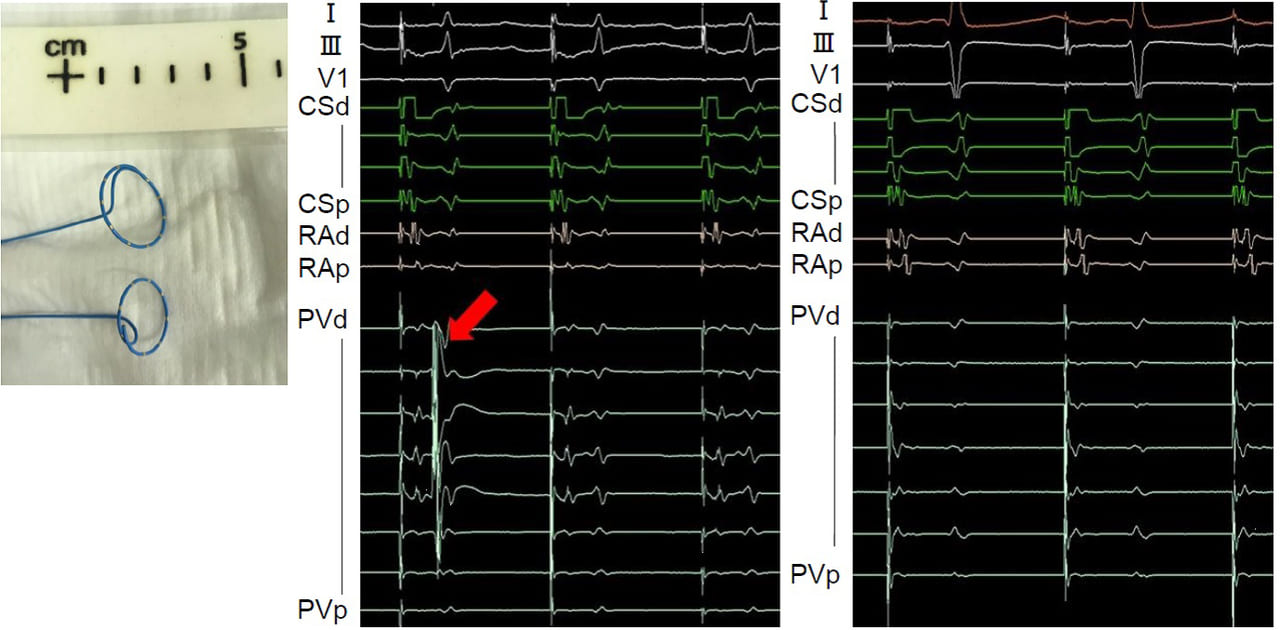

A decapolar 25-mm-diameter circular mapping catheter with improved detection of pulmonary vein potential disappearance in cryoballoon ablation.

Matsuda Y, Masuda M, Asai M, Iida O, Okamoto S, Ishihara T, Nanto K, Kanda T, Tsujimura T, Okuno S, Tsuji A, Mano T. J Arrhythm 2019;35:535-541.